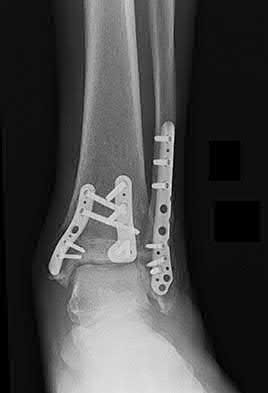

Question 18:

A 60-year-old diabetic patient presents with a warm, swollen, erythematous foot. Radiographs reveal fragmentation of bone, periarticular debris, subluxation, and joint dislocation. There is no active consolidation. Which stage of the Eichenholtz classification for Charcot arthropathy does this represent?

Correct Answer: Stage I (Developmental/Fragmentation)

Explanation:

The Eichenholtz classification describes the natural history of Charcot neuroarthropathy. Stage I (Developmental/Fragmentation) is characterized by acute inflammation, osteopenia, joint subluxation/dislocation, bone fragmentation, and intra-articular debris. Stage II (Coalescence) shows decreased inflammation and early absorption of debris. Stage III (Consolidation) shows remodeling and robust bony fusion. Stage 0 was later added (Shibata) to denote the acute inflammatory phase prior to radiographic fragmentation.